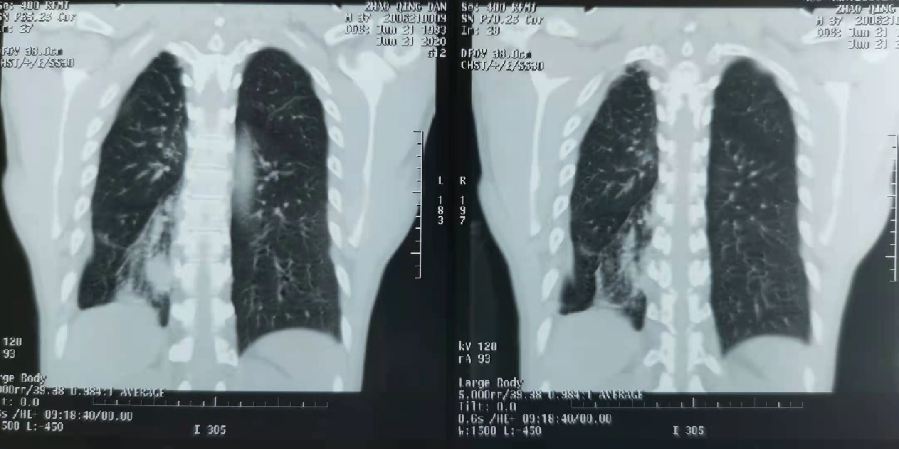

根據《西安新聞網》報導,西安一名40歲的男病患,長期咳嗽、咳痰長達20年,沒想到近一年,他的病情卻開始加重,不僅痰中出現血,就連血量也逐漸增加、呈現鮮紅色,眼看病情危急,他便到西安市中心的醫院檢查,經醫師診斷,並照胸部X光,這才發現他的氣管中有異物。

▼男子長期有咳嗽的症狀。(圖/翻攝自西安新聞網)